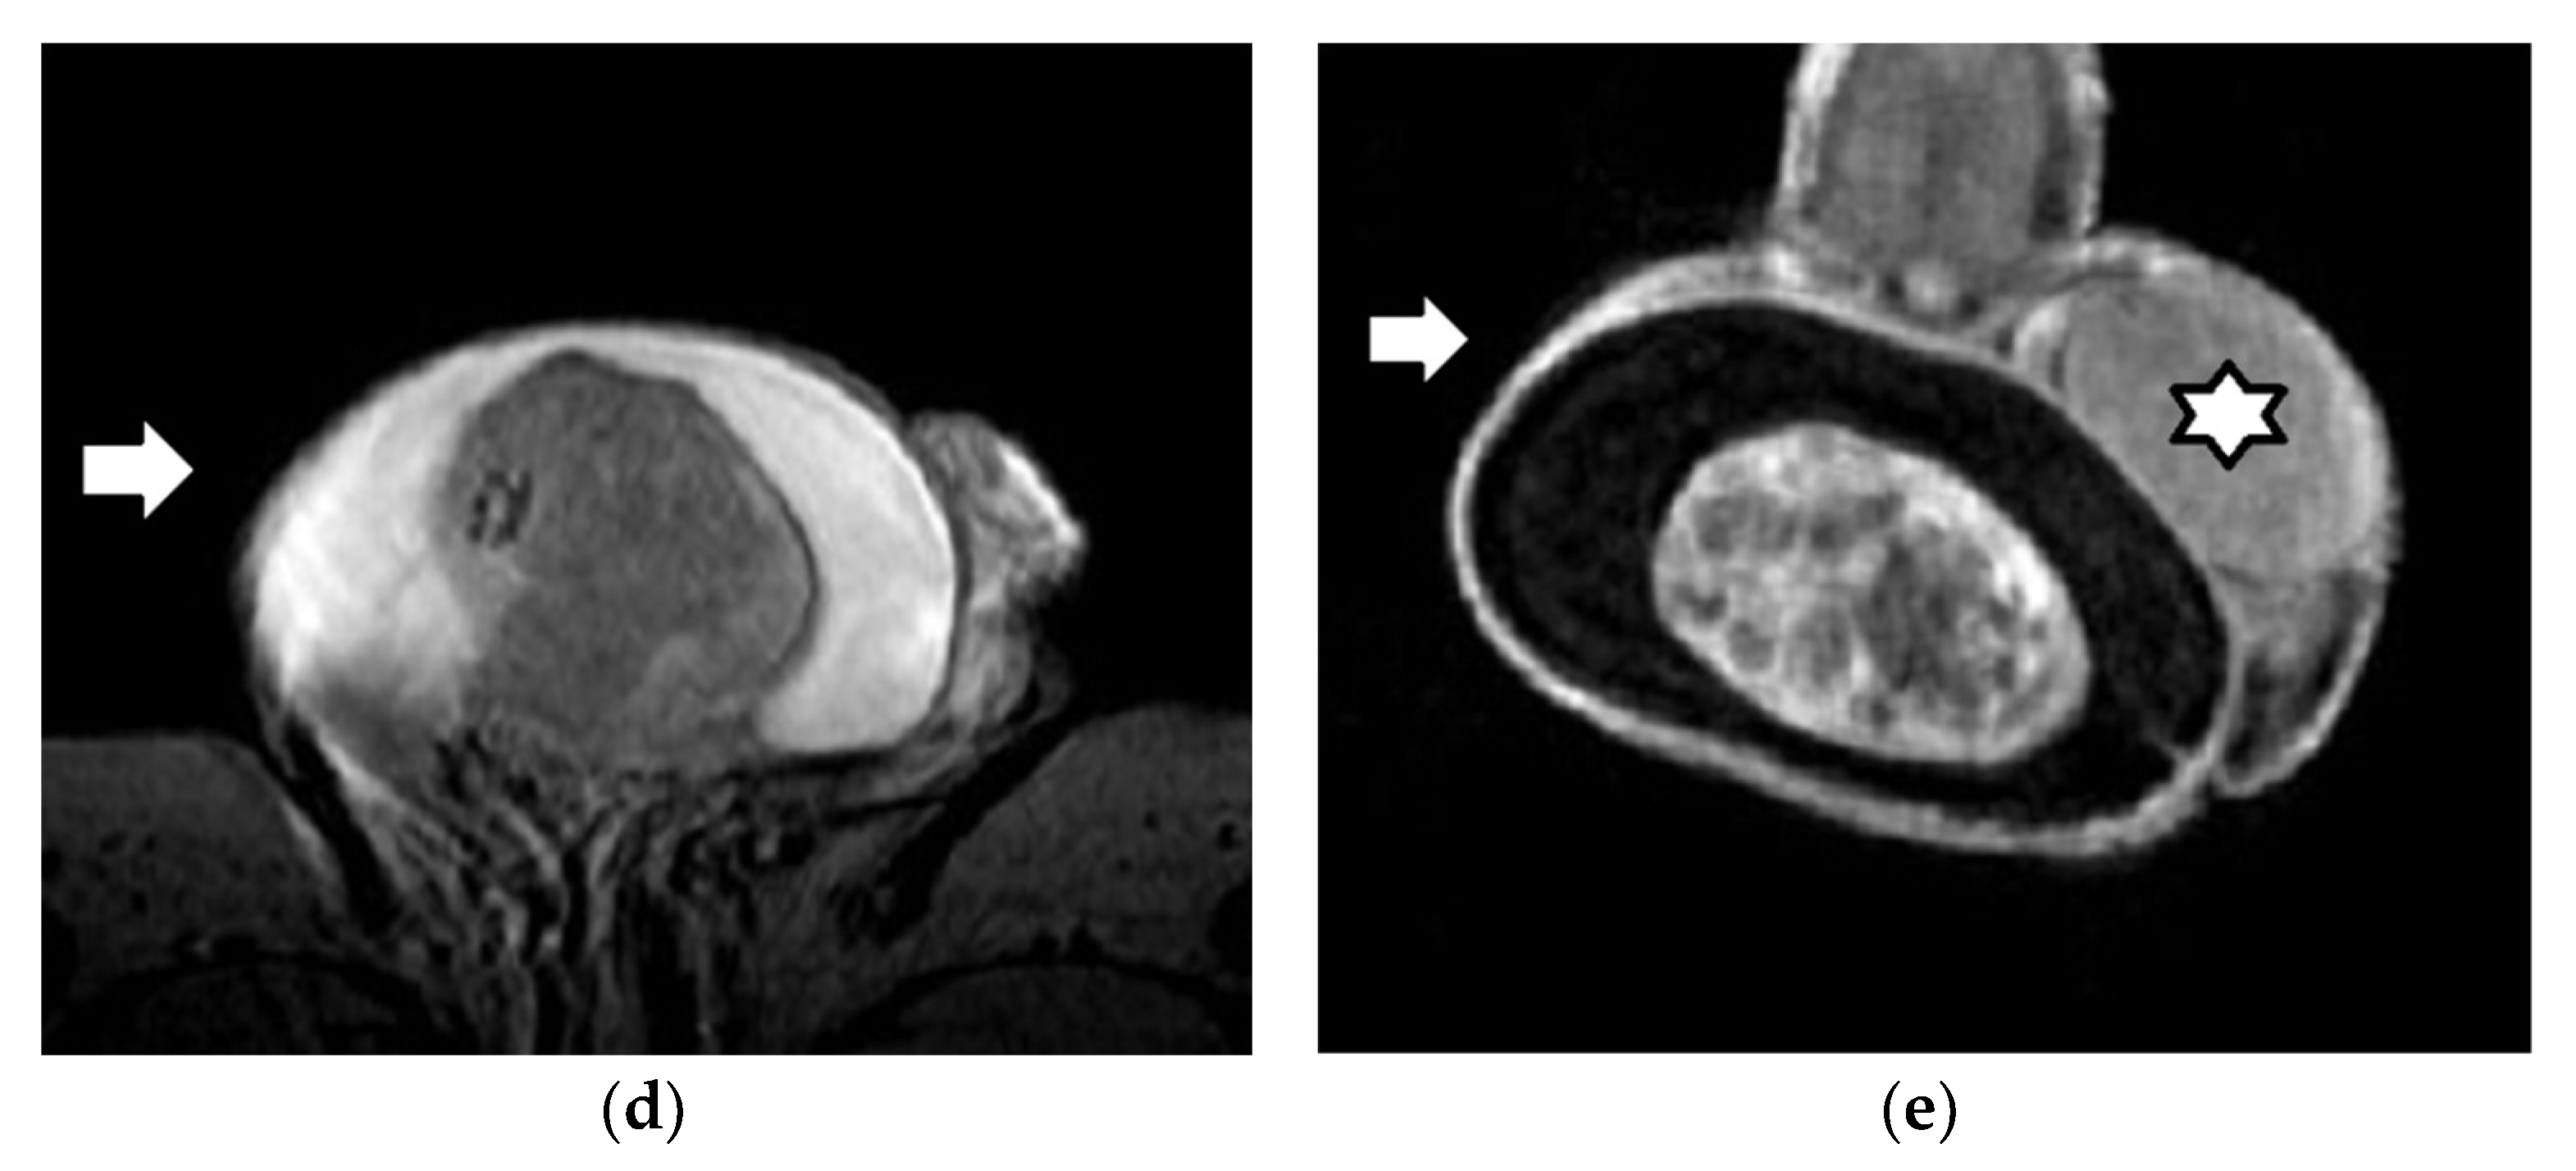

3.2. Epidermoid Cysts

3.3. Testicular Lymphoma